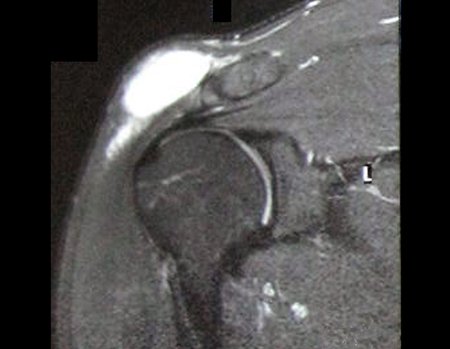

Luego se realizó una resonancia magnética cuyas imágenes principales se muestran en las figuras 5 a 10.